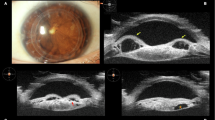

Purpose To determine the use of high-frequency ultrasound biomicroscopy (UBM) in the assessment of inflammatory lesions of the iris, ciliary body, pars plana and peripheral vitreous, and in particular to determine the proportion of cases for which UBM contributed significant additional, hitherto inaccessible, information.

Methods Charts of patients seen in the uveitis clinic at University Eye Hospital from November 1994 to September 1999 for whom a UBM investigation had been performed were analysed. UBM was performed in a standard manner, using a Humphrey UBM 840 system. The clinical relevance of the UBM findings was determined for the whole series and for the following six subgroups of patients arbitrarily established according to the type and location of pathology: hypotony, pseudophakic uveitis, iris and ciliary body pathology excluding hypotony, pars plana pathology, scleritis and Toxocara uveitis. Findings were classified as positive when they confirmed a suspected diagnosis of lesional process or when they gave essential information. Findings were classified as essential when they led to the diagnosis or when they modified therapeutic intervention.

Results During the study period 111 eyes of 77 patients were included. UBM findings contributed essential information that allowed a diagnosis to be reached or that influenced treatment in 43% of cases. It yielded positive findings in 91% of cases, enabling assessment of morphological changes in the iris, ciliary body, and retroiridal and peripheral vitreous induced by intraocular inflammatory or pseudo-inflammatory disorders. Specific UBM signs, present in all patients, were identified in Toxocara uveitis. The groups of patients that benefited most from UBM examination were those with hypotony (83% essential findings) and opaque media (100% essential fidings).